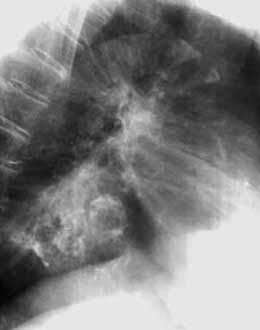

Рис. 3. Грыжа пищеводного отверстия диафрагмы. (Слева) На прямой ренгенограмме грудной клетки дополнительная тень в правом кардио-диафрагмальном угле. (Справа) На правой боковой ренгенограмме грудной клетки добавочная тень в заднем средостении.